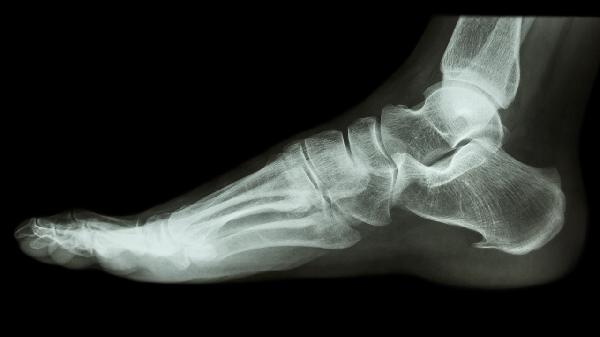

足跟骨折后遗症是什么 足跟骨折的3个后遗症揭晓

足跟骨折后遗症主要有创伤性关节炎、足跟畸形愈合、慢性疼痛。足跟骨折通常由高处坠落、交通事故等外力冲击导致,可能影响行走功能和生活质量。

足跟骨折后应定期复查X线观察愈合情况,康复期避免剧烈跑跳运动。饮食注意补充钙质和维生素D,可适量增加牛奶、西蓝花等食物。若出现持续肿胀或夜间静息痛,需及时排查缺血性骨坏死等并发症。建议选择硬底缓冲鞋减少行走冲击,睡眠时用枕头垫高患肢促进静脉回流。